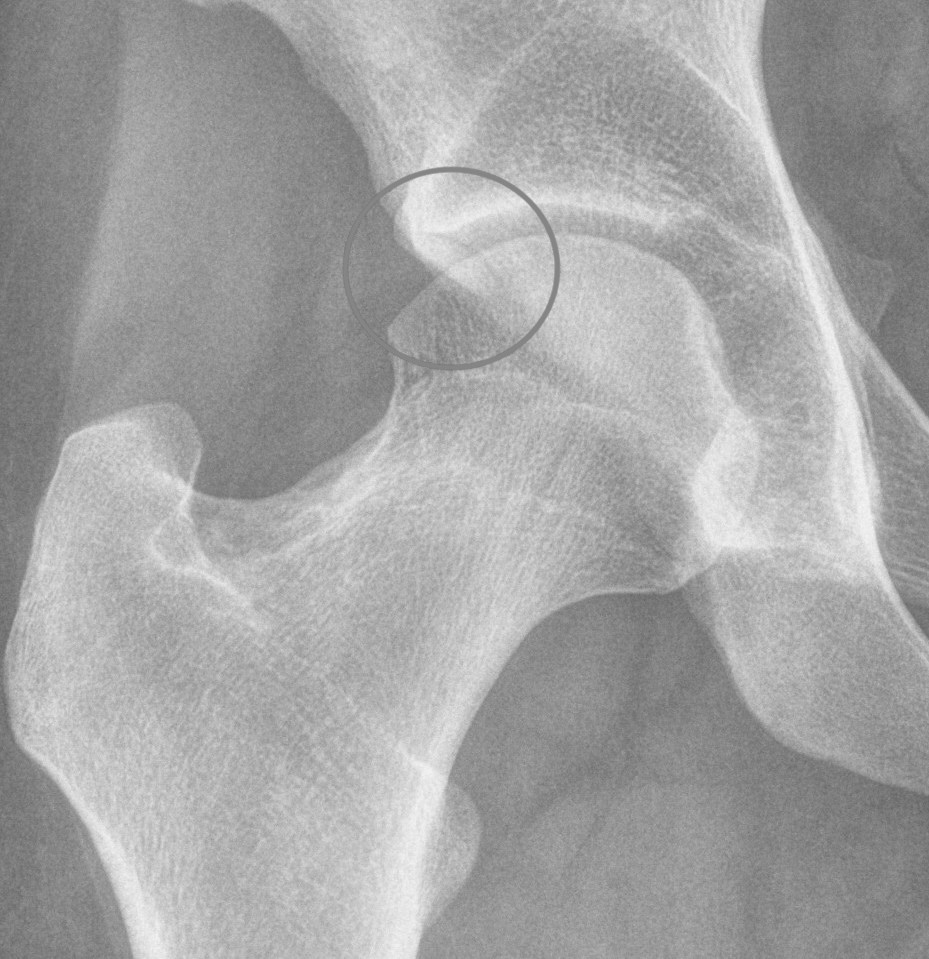

Alpha angle

Measurement

- centered in the center of the femoral head (best fit circle)

- formed by two lines

- one line center of the femoral neck axis

- a line where the femoral head leaves a best-fit circle

- higher alpha angle with Cam lesion